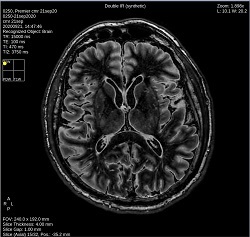

- By default, a 6-viewport display is launched with 6 unique MAGiC images.